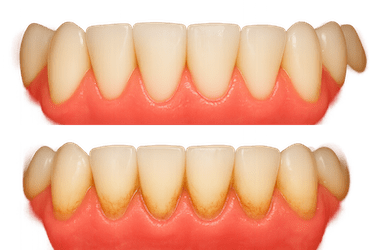

- Encías inflamadas o con alteraciones de color: es otro claro síntoma de que hay enfermedad periodontal. Pueden hincharse y ponerse tanto de color rojo brillante como de un tono más oscuro.

Existen diferentes tipos de tratamiento de periodoncia. Dependiendo de tu caso tendremos que optar por uno u otro. Los más comunes son limpiezas completas en los casos iniciales de enfermedad periodontal, curetajes y alisados radiculares para tratar la periodontitis leve e injertos en los más avanzados. En los casos más graves será necesario recurrir a cirugías periodontales.

Injerto conectivo o matrices de colágeno para cubrir recesiones y aumentar encía queratinizada. Disminuye la sensibilidad y protege raíces o implantes.